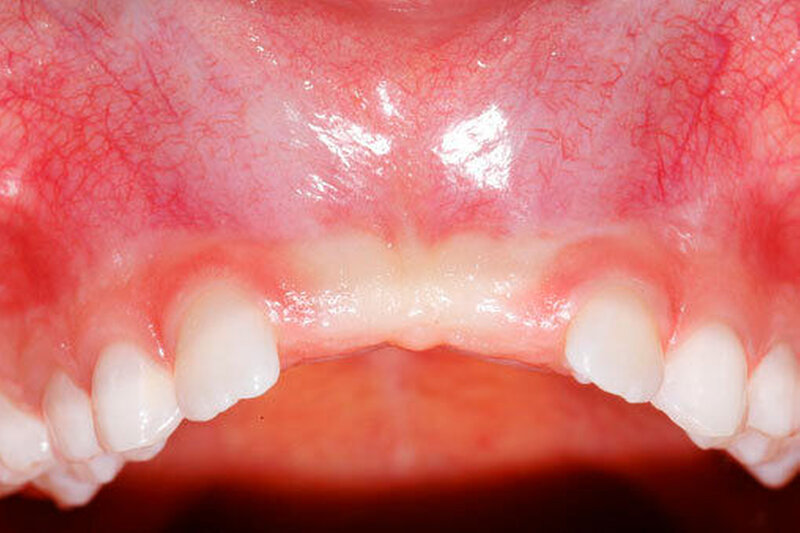

Die Prävalenz überzähliger Zähne wird im Bereich von 0,07 Prozent bis 0,6 Prozent für das Milchgebiss [Luten, 1967; Ravn, 1971; Järvinen Lehtinen, 1981; Magnússon 1984; Skrinjari Barac-Furtinovi, 1991; Yonezu et al., 1997; Chen et al., 2010] und von 0,3 Prozent bis 3,2 Prozent für die bleibenden Zähne [Luten, 1967; Bäckman Wahlin, 2001; Salcido-García et al., 2004; Leco Berrocal et al., 2007; Gündüz et al., 2008; Yagüe-García et al., 2009; Schmuckli et al., 2010; Fardi et al., 2011] angegeben. Die Mehrheit der überzähligen Zähne im Milchgebiss sind seitliche Schneidezähne im Oberkiefer, die meist mit einer normalen Morphologie und Lage durchbrechen (Abbildungen 1 bis 3) [Luten, 1967; Humerfeld et al., 1985; Garvey et al., 1999; Ferrés-Padró et al., 2009]. Der oft ungestörte Durchbruch und das Ausbleiben von Symptomen führen dazu, dass überzählige Zähne in der Milchdentition oft gar nicht diagnostiziert werden, und dies wird auch als Erklärung für die unterschiedlichen Prävalenzen überzähliger Zähne im Milch- und bleibendem Gebiss angeführt [Wang Fan, 2011]. Überzählige Zähne sind häufiger bei Männern als bei Frauen, wobei über ein Verhältnis von 1,18:1 bis 4,5:1 berichtet wird [Rajab Hamdan, 2002; Fernández Montenegro et al., 2006; Gündüz et al., 2008; Wang Fan, 2011]. In der Schweiz publizierten von Arx (1990) und Schmuckli und Mitarbeiter (2010) Geschlechterverhältnisse von 2,6:1, beziehungsweise 2,75:1. In einer aktuellen Arbeit von Mossaz und Mitarbeiter (2014) von Patienten aus dem Raum Bern lag dieses Verhältnis etwas ausgeglichener bei 1,61 zu 1.

Überzählige Zähne können einzeln oder multipel auftreten [von Arx, 1990; Rajab Hamdan, 2002; Fernández Montenegro et al., 2006; Liu et al., 2007; Gündüz et al., 2008; Ferrés-Padró et al., 2009; Hyun et al., 2009]. Einzelne überzählige Zähne treten in 65,8 bis 80,5 Prozent, doppelte in 14,5 bis 27,7 Prozent und multiple in 0,6 bis 8 Prozent der Fälle auf [Rajab Hamdan, 2002; Fernández Montenegro et al., 2006; Liu et al., 2007; Ferrés-Padró et al., 2009; Hyun et al, 2009; Mossaz et al., 2014]. Einzelne oder doppelte überzählige Zähne finden sich typischerweise in der Oberkieferfront [Rajab Hamdan, 2002; Fernández Montenegroet al., 2006; Mossaz et al., 2014]. Multiple überzählige Zähne werden vor allem im Prämolarenbereich des Unterkiefers gefunden [Abbildung 4; YUSOF 1990, Ferrés-Padróet al., 2009; Wang Fan, 2011]. Multiple überzählige Zähne sind zudem oft mit anderen Erkrankungen oder Syndromen assoziiert, dazu gehören Lippen-Kiefer-Gaumenspalten, die cleidokraniale Dysplasie oder auch das Gardner-Syndrom. Bei Patienten mit einer Lippen-Kiefer-Gaumenspalte wird vermutet, dass sich die überzähligen Zähne aus der Fragmentierung der dentalen Lamina bei der Spaltbildung ergeben [Garvey et al., 1999; Wang Fan, 2011].